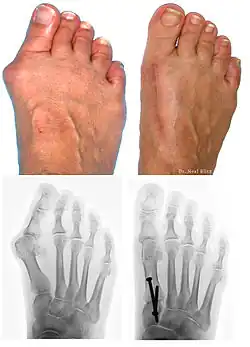

L’hallux valgus (HV, du latin hallus, gros orteil et valgus : « tourné en dehors »), souvent accompagné d'un « oignon » (callosité de la peau en regard de la déformation), est une déformation du pied correspondant à la déviation du premier métatarsien en varus (en dedans) et du gros orteil (hallux) en valgus (en dehors).

Bilan radiographique

Le diagnostic est avant tout clinique, mais des radiographies sont indispensables pour mesurer la déformation et adapter la technique chirurgicale aux spécificités du patient. Les radiographies doivent être effectuées de façon rigoureuse : clichés d'avant-pied de face, profil, et 3/4, patient debout en charge. Ce dernier critère est indispensable car le squelette du pied adopte des positions dans l'espace qui diffèrent selon que le poids du corps repose ou non sur lui. C'est l'état du squelette debout en charge qui doit guider le geste chirurgical.